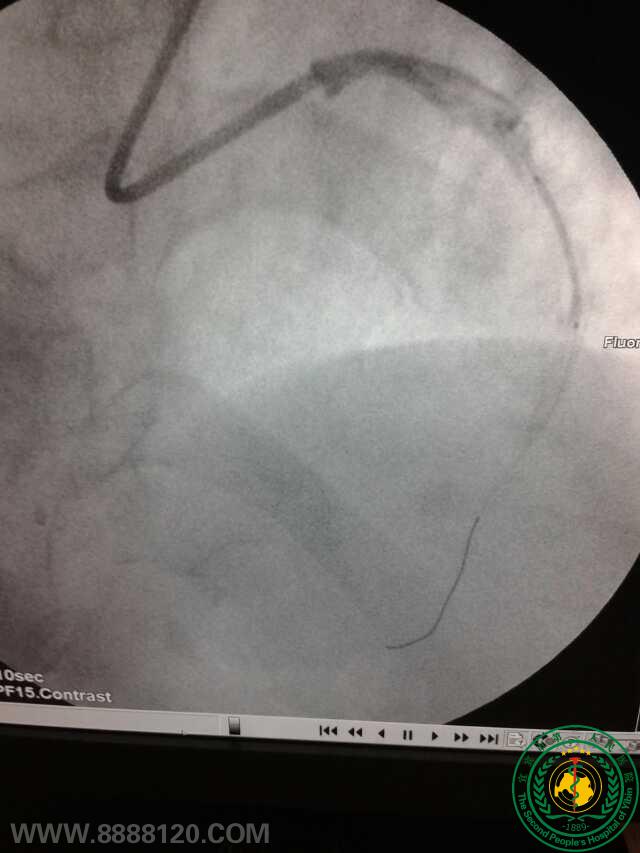

冠脉治疗新技术——宜宾首例冠脉旋磨术

宜宾市第二人民医院 图文